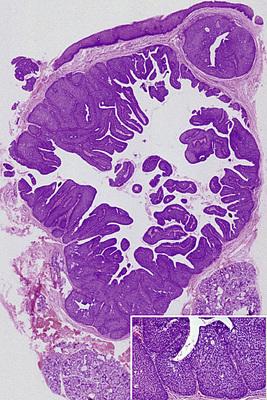

- Low-power photomicrograph showing a cyst below the mucosal surface.

- High-power view of cystic cavity lined by thin cuboidal epithelium. Adjacent to the cyst is an excretory salivary gland duct lined by columnar epithelium.

salivary duct cyst

This dilated duct is lined by columnar eosinophilic oncocytes that exhibit papillary folds into the ductal lumen. Such lesions may develop secondary to ductal obstruction.

salivary ductal ectasia